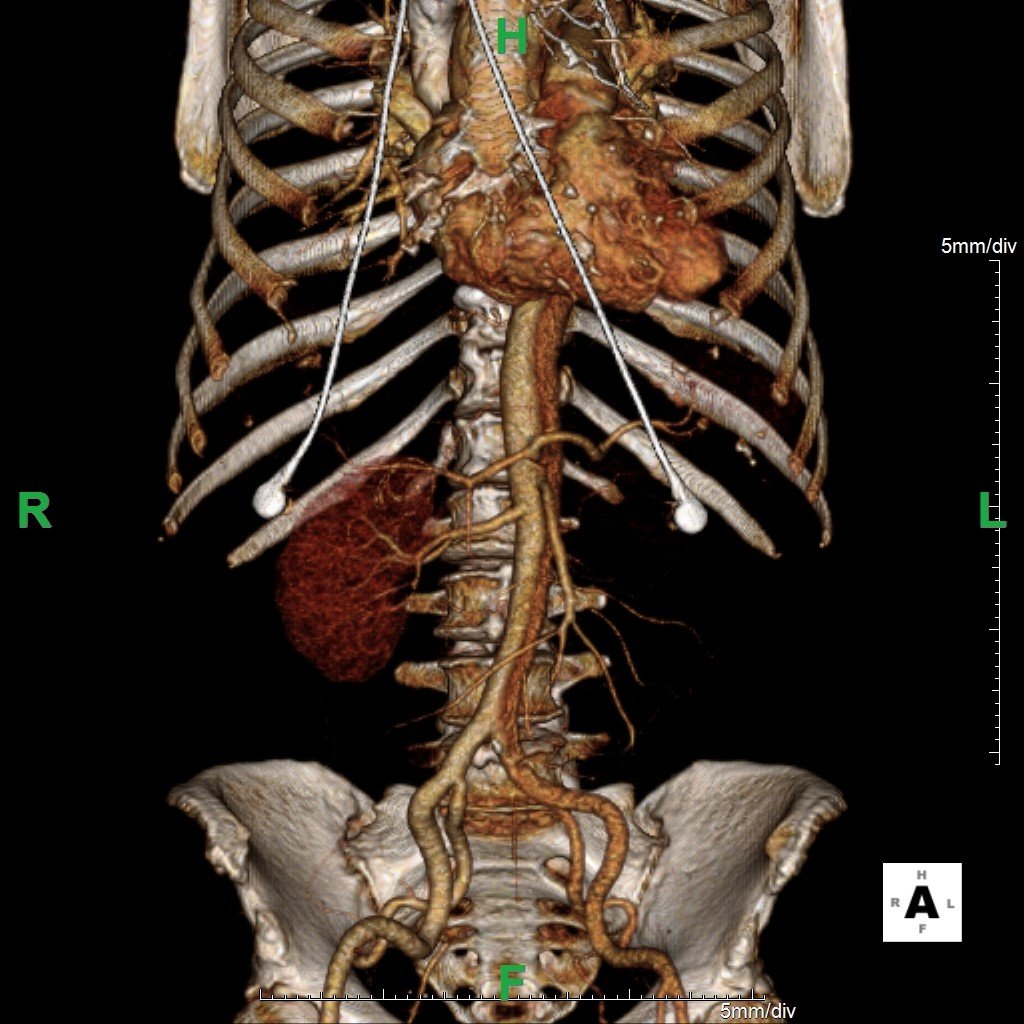

Because aortic dissection was suspected, the patient underwent urgent computed tomography (CT) angiogram of her chest, abdomen and pelvis that revealed her diagnosis.

The patient was found to have a Stanford type A dissection (see yellow arrow) with visible false lumen starting at aortic arch (see green circle). The dissection extended into the descending aorta (see blue circle) as shown by the false lumen (red highlighted area) visible on CT. The radiologist performed a reconstruction of the aorta, which showed that the left kidney was not being perfused, making the kidney not visible on the reconstruction.